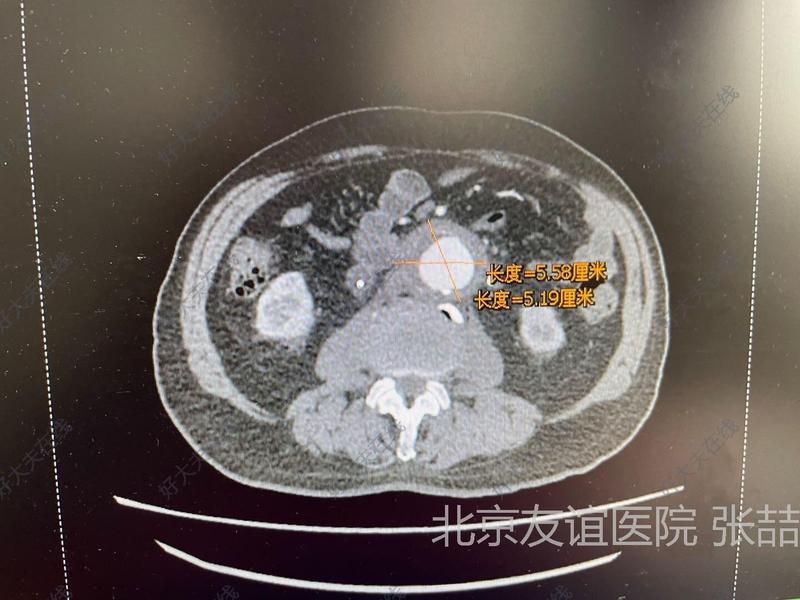

右颈部淋巴结转移性甲状腺乳头瘤癌记录患者于2018年8月首次在中医处诊治出甲状腺结节,随后前往空军总医院进行超声检查,并咨询友谊医院穿刺预约了内分泌科医生,医生建议定期复查2018年11月,患者在复查时,彩超医生建议前往301医院进行穿刺以进行病理分析然而,由于患者对病情了解不足,加之病情发展缓慢,以及个人对。

友谊医院在肝内胆管结石治疗方面积累了大量的临床经验,尤其擅长于微创手术治疗该医院引进了国际先进的微创技术,如腹腔镜经皮穿刺等,能够有效减轻患者的痛苦,提高手术成功率医院还注重术后康复指导,为患者提供个性化的康复方案,帮助患者早日恢复健康友谊医院拥有完善的预约挂号系统,患者可以通过电话。

罗渝坤主任特点专业性强能准确区分淋巴结增生与癌转移例如,用户在北京协和友谊医院华西医院四川省中医院四川省人民医院等多家医院就诊时,部分医生误将淋巴结增生诊断为癌转移并建议切除手术,而罗主任通过专业判断指出95%的“转移小黑点”实为淋巴增生,后续手术淋巴穿刺结果也证实为正常。